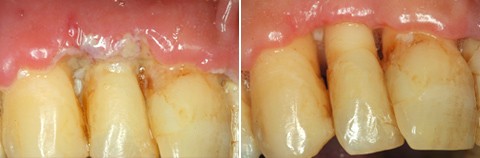

Abb. links NUG einer 37-jährigen Patientin mit interdentaler Nekrose in Regio 32/33. Anamnestisch ergab sich ein Alkoholabusus bei einer ansonsten gesunden Patientin.

Abb. rechts Kontrolle fünf Tage nach mechanisch-medikamentöser Initialtherapie: deutlicher Rückgang der klinischen Entzündungszeichen und Verlust der interdentalen Papille in Regio 32/33.